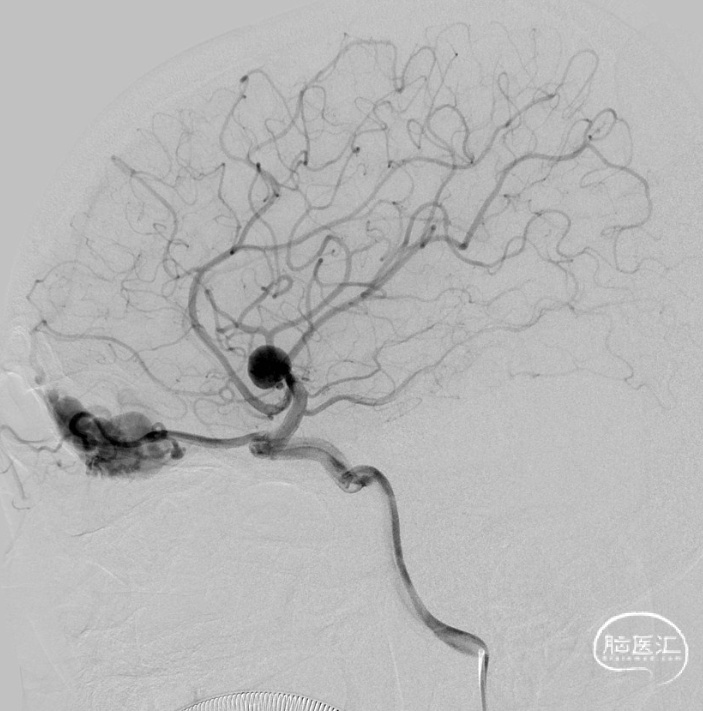

治疗经过

· 病例小结 ·

二期治疗